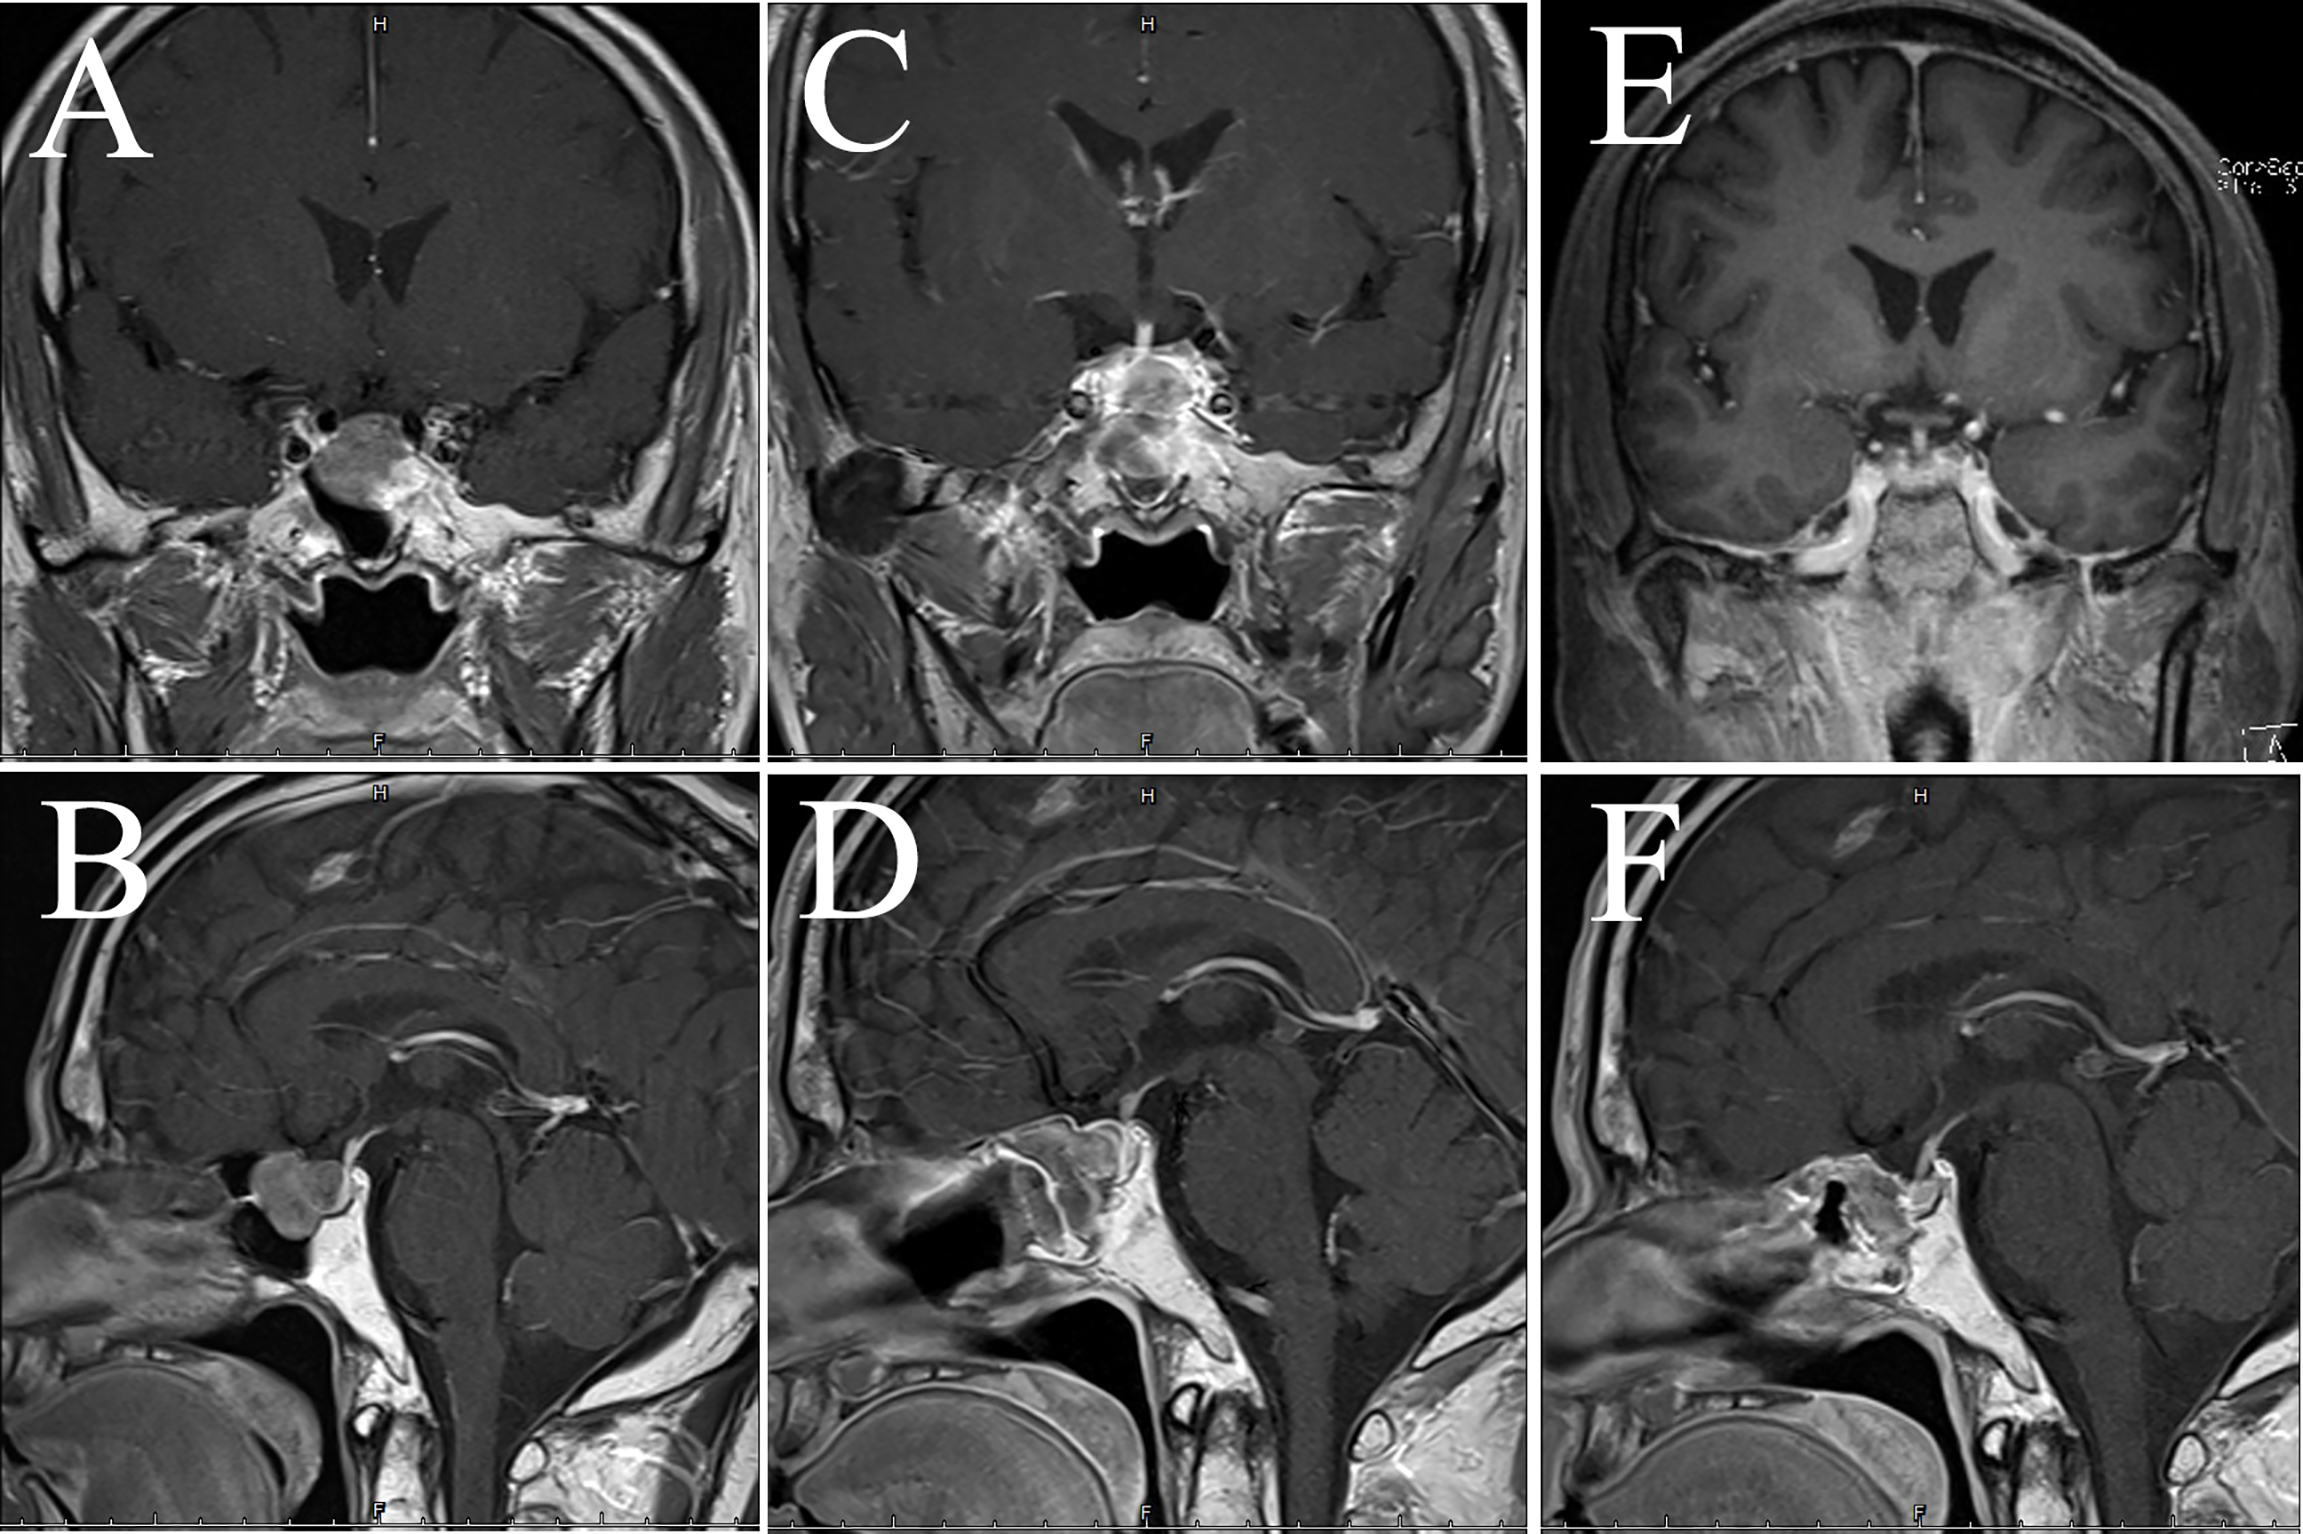

Figure 4

Imaging data of case 2. The images show coronal and sagittal MRI of the patient’s head preoperatively (A, B), three months postoperatively (C, D), and twenty-one months postoperatively (E, F), respectively.